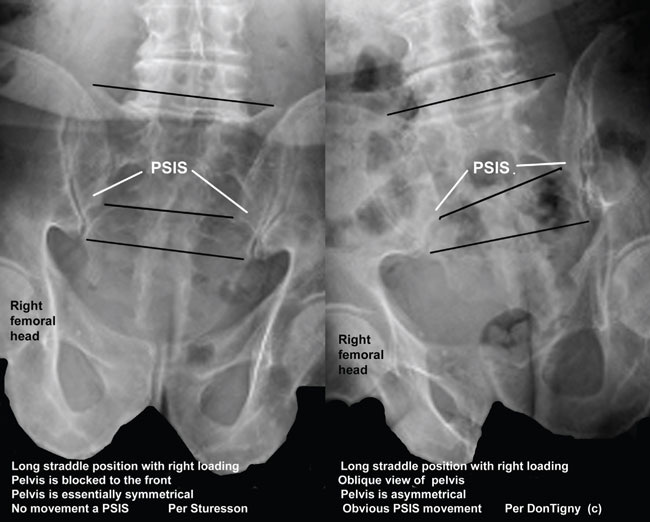

Many practitioners believe that the sacroiliac joint does not move more than just a few degrees. Even though Smidt measured up to 30 degrees of motion with the patient in the long straddle position, as if taking a long step (). Sturesson measured a subject in the long straddle position and found movement in the sacroiliac joint of only about 5 degrees (). Most physicians accept Sturesson's measurements, which were extremely accurate. In examining the method used by Sturesson I found that he had made an inadvertent error in his positioning that was responsible for a substantial error in the amount of movement measured. Most practitioners accept Sturesson's measurements as accurate, leading to the myth that the sacroiliac joint essentially has no movement and no important function.

I have demonstrated this movement on x-ray and put it on this website rather than publish the information. Although publishing provides some stature it limits access to those professionals who may subscribe to any specific journal.

X-rays taken of a pelvis in the long straddle position with counter rotation and with loading to the right and to the left.

In order to view innominate movement on the oblique asymmetric pelvis it was necessary to have the front of the pelvis square to the camera, but oblique to the line of travel.

Movement of the posterior superior iliac spines on the sacrum is obvious and much greater than reported. Clearly, there is ample movement at the sacroiliac joint and not minimal as is commonly believed. This position is clearly static. Dynamic movement would surely demonstrate greater movement than presently observed.

Sturesson had the subject with the direction of travel straight into the camera and with the pelvis perpendicular.

click

to enlarge

DonTigny ©

Sturesson did not have the pelvis in an oblique or asymmetrical position nor did he include counter rotation. Although his measurements were extremely accurate in this position he inadvertently measured some slight movement on the symmetrical pelvis rather than normal movement on the oblique pelvis with counter rotation.

X-rays were taken of the subject in the long straddle position with loading on the right. The x-ray on the left is with the pelvis as per Sturesson, with travel toward the front, no asymmetry and no counter rotation. The one on the right is with the pelvis facing the x-ray, with the direction of travel oblique to the x-ray, the pelvis is asymmetrical and with counter rotation to the right.

Conclusion: The sacroiliac joint demonstrates ample movement during normal ambulation when the pelvis is oblique to the line of travel and with counter rotation to the right and left.